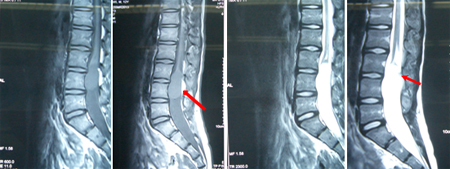

男性,12岁,间断腰臀部疼痛4年。鞍区针刺痛觉减退,腰后部可见皮毛窦、不分泌,下腹壁和双侧跟腱反射减弱,双下肢位置觉障碍。术前图片: